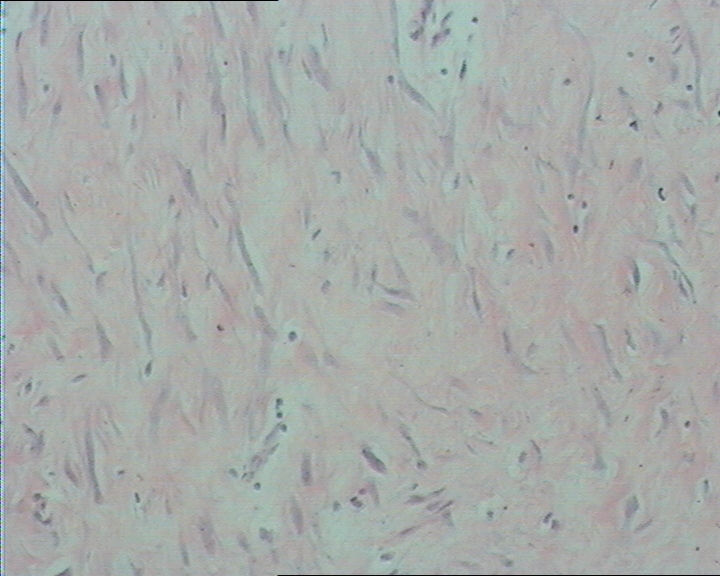

右肘部肿物

图4

右肘部肿物,无包膜,3.8cm*3.0cm*2cm,切面灰白淡黄相间。